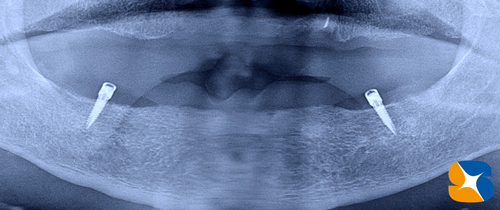

昨年の暮れにインプラントを移植された方の初めての定期検診。

72歳の男性。永年、上も下も全部入れ歯を使っておられました。上の全部入れ歯は、ポリグリップで外れないようにがっちりキープ出来ています。しかし、下の全部入れ歯は、大きな口を開けると動いて外れそうになるので何か良いものはないかな?がこの治療の始まりでした。

下のアゴに2本の(ロケーター)インプラントを移植しました。

たった2本のインプラントですが、全部入れ歯は全く動きません。